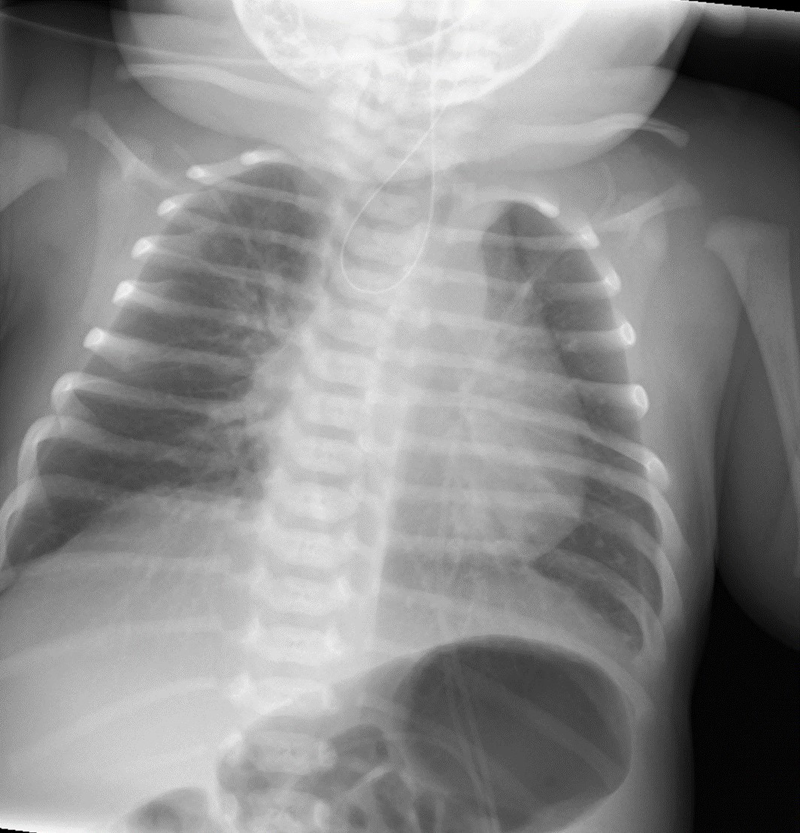

Recién nacido a término con embarazo normoevolutivo, sin hallazgos significativos en las ecografías prenatales y parto sin complicaciones. Avisan a las 7 horas de vida por abundantes secreciones orofaríngeas y dificultad respiratoria. A la exploración se objetiva abundante sialorrea, auscultándose ruidos de secreciones de vías altas.